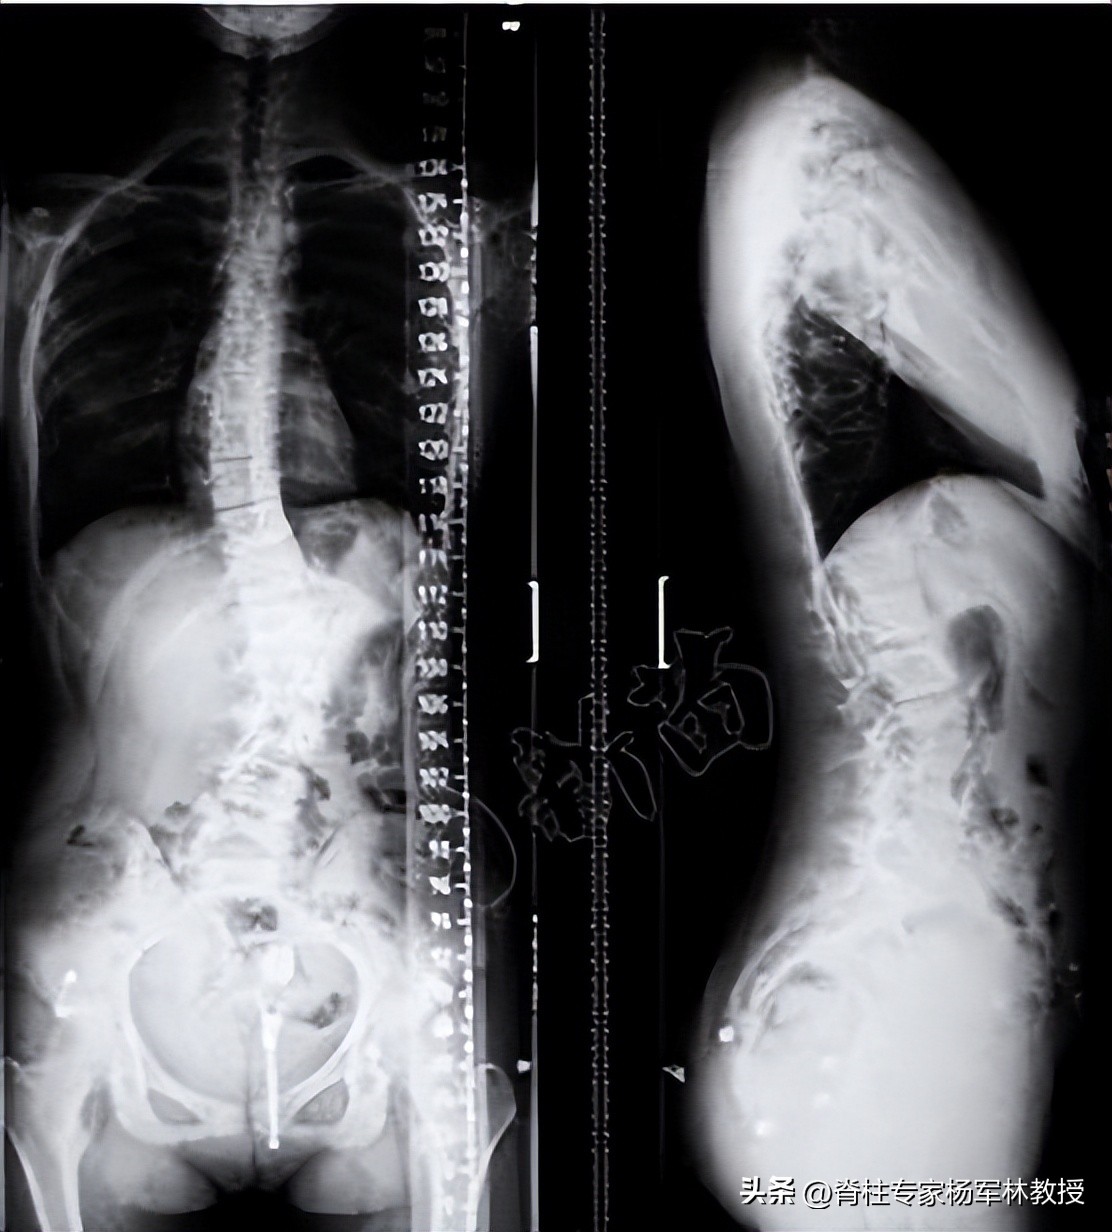

标准全脊柱X光片拍摄指南

标准的全脊柱X光片是怎么样的?

正位片

侧位片

拍摄全脊柱X光片需要注意什么?

1、采取站立位。

2、包含下颈椎、双肩和双髋关节的全脊柱正位片和侧位片。

3、脱鞋拍摄,避免因鞋子磨损过多等造成脊柱偏移。

4、拍正位片时,保持双手垂立两侧,端正站姿。

5、拍侧位片时,双拳紧握稍贴脸部和下颌部、肘关节稍贴胸前,保持直立站姿,不要前伸或后仰。

6、简单着装,避免金属配饰的干扰。